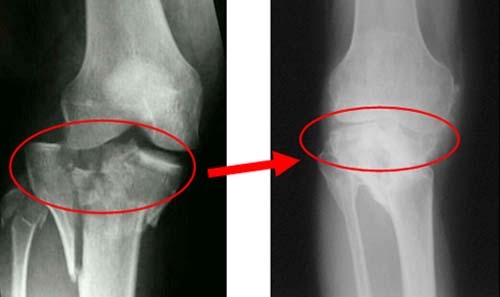

После поступления пострадавшего в медицинское учреждение травматолог назначает рентгенографию. Если есть подозрение на повреждение мениска, могут быть рекомендованы МРТ или УЗИ. При переломах костей первым шагом является удаление скопившейся в суставе крови и обеспечение обезболивания. Затем накладывается гипсовая лонгета или наколенник (брейс), изготовленный из материалов, способствующих быстрому срастанию костей. Для восстановления хрящей назначаются хондропротекторы.

Если перелом сопровождается смещением, потребуется хирургическое вмешательство. В ходе операции остеосинтеза удаляются скопления крови, осколки костей возвращаются в правильное положение и фиксируются с помощью штифтов, винтов и пластин. При повреждении кожи осколки фиксируются с использованием аппарата Илизарова.